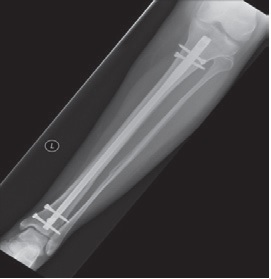

How will my bone be fixed?

Open fractures almost always need surgery to put the bone back and hold it there while it heals. This can be done in a number of ways. Examples are shown below. Your surgeon will discuss with you what he/she feels is in your best interest.

What is external fixation?

External fixation is when pins or wires into the bone are attached to rings or rods outside the limb. External fixators are used commonly as a temporary measure but can also be used as the final treatment and removed once the bone has healed.

What is internal fixation?

Internal fixation is when either a rod inside the bone or plates on the surface of the bone are fixed to the bone with screws. These generally stay in forever but can be removed if there are any problems, but this is very uncommon.